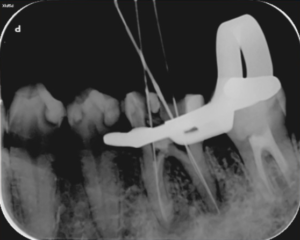

治療中

歯の根の治療中のレントゲン写真です。

歯の根の中を清掃する器具を入れています。根の中のばい菌を除去してきれいにしています。

歯の根の中を清掃し終わった後に内部に薬を詰めた直後のレントゲン写真です。

薬は根の中に緊密に詰まっています。一部先から漏れている部分もありますが、のちに吸収されていきます。